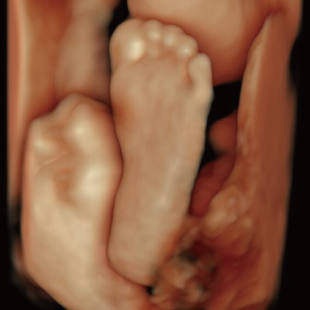

妊娠中期になると、胎児の体や内臓の構造がよりはっきりと確認できるようになります。 中期スクリーニングでは、頭部、顔面、頸部、胸部、腹部、心臓、手足、外性器、臍帯や胎盤など、全身をくまなく観察し、形態の状態を詳しく確認します。この頃に染色体数の変化を疑わせる所見が確認される事もあります。

胎児ドックの様子_中期_頭 胎児ドックの様子_中期_顔面 胎児ドックの様子_中期_心臓 胎児ドックの様子_中期_腹部 胎児ドックの様子_中期_足 胎児ドックの様子_中期_4D

妊娠後期は、胎児の成長がさらに進み、発育の途中で現れてくる変化を確認できる時期です。中期の検査では問題が見られなかった場合でも、成長に伴って形態の変化が現れることがあります。また、構造だけではなく、胎児機能(赤ちゃんの元気度)の評価も可能となります。後期スクリーニングでは、各臓器の状態や構造に加え心臓の動きや血液の流れなどをより詳しく観察します。

胎児ドックの様子_後期_頭 胎児ドックの様子_後期_心臓 胎児ドックの様子_後期_心臓 胎児ドックの様子_後期_足 胎児ドックの様子_後期_4D